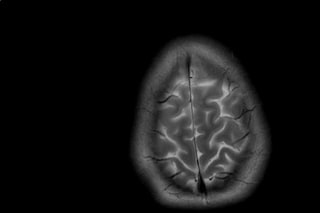

Courtesy the artist and all in: the mindArt & Photography / LightboxArt & Photography / LightboxArtists come together to break the stigma of mental healthAkinola Davies, Gary Card, Campbell Addy, Gaika, Holly Blakey, and more, use their art to fuel a discussion in self-care, self-medication, and self-awareness – preview it hereShareLink copied ✔️August 10, 2017August 10, 2017TextLottie HodsonBryony Stone’s all in: the mind An IRL platform started by writer and curator Bryony Stone, which goes under the alias ‘all in:’ launches tonight, with the aim to use art to gather people together, spark consequential discussions and act as a catalyst for social change in regards to mental health. As an accessible, online community, ‘all in:’ provides a space for fresh ideas and personal experiences to be shared. “I started ‘all in:’ as an IRL platform which uses art as a springboard to provoke meaningful conversations,” Stone explains. “Talking about mental health can be intimidating because it’ so often so personal and tangled up in emotion.” “There is so much pressure to perform for creatives” – Bryony Stone For almost a year she has been thinking about all in: the mind – an exhibition dedicated to mental health awareness in the hectic creative industry. Stone says, “There is so much pressure to perform for creatives…I wanted to remind people that they aren’t alone by establishing a framework where these conversations could be had.” In a pursuit to break the silence surrounding mental health, this 10-day exhibit brings together 19 artists from all realms of the creative world. Despite their different outcomes, each artist shares the hunger of pushing the boundaries of their mediums to see what they can achieve, often resulting in experimental, outspoken work. From Campbell Addy to Gary Card to Gaika, each creative offers “their own unique perspective on mental health, bringing their own experience to the show and adding their voice to a purposefully diverse collective narrative.” Although forming a universal sentiment of acceptance and openness, visitors can expect to see an all-embracing mix of visual representations and interpretations of mental health. Whether discussing welfare in creative communities, drug use or the effect of political events on mental health, the artists of all in: the mind speak up about how mental health manifests itself in them personally. Margot Bowman’s Sommer of HateCourtesy the artist and all in: the mind Sharing a common ground in what they all call home, these London-based artists will be presenting their work in the arches underneath Waterloo station at House of Vans; Stone divulges the city’s critical impact on the exhibition. “So consciously or subconsciously, the city becomes a subtext, looming in the background of each of the artist’s very different experiences.” By bringing together industries, people and art Stone offers a safe haven for those struggling with mental health, “some openly, others behind locked loo cubicle doors”. Holly Blakey’s Mica Levi WrathCourtesy the artist and all in: the mind all in: the mind opens at London’s House of Vans on Thursday 10 August at 7pm and will run until 20 August 2017. A mental health and creativity panel discussion will be held on 17 August from 7pm. Artists involved include Akinola Davies, Margot Bowman, Gaika, Holly Blakey, Mica Levi, James Massiah, A Sai Ta, Joy Miessi, Tim Noble, Celia Hempton, Diana Chire, Tom Mattison, Gary Card, Liam Hodges, Suzannah Pettigrew, Campbell Addy, Joey Yu, Sienna Murdoch and Hannah Perry Escape the algorithm! Get The DropEmail address SIGN UP Get must-see stories direct to your inbox every weekday. Privacy policy Thank you. You have been subscribed Privacy policy Expand your creative community and connect with 15,000 creatives from around the world.READ MOREUncensored photos from Tokyo’s longest-running fetish nightCova da Moura: Vibrant portraits from the hip-hop capital of LisbonThese dreamy portraits rebel against stereotypes of Asian youth cultureLenovo & IntelWatch: How three artists make space for AI, creativity and worldbuildingDazed Club callout! Apply to bring your exhibition project to lifeUS fascism is killing artSee Nan Goldin’s The Ballad of Sexual Dependency in LondonIn pictures: The nostalgia-fuelled traditions of Ukraine’s lost townsThese photos explore the uncanny world of love dolls Arresting portraits of Naples’ third-gender population 10 major photography shows you can’t miss in 2026This exhibition uncovers the queer history of Islamic artEscape the algorithm! Get The DropEmail address SIGN UP Get must-see stories direct to your inbox every weekday. Privacy policy Thank you. You have been subscribed Privacy policy